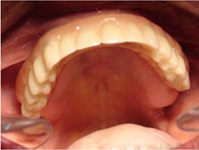

Pevné můstky – lepené nebo šroubované

S pomocí zubních implantátů můžeme díky různým kotevním systémům (třmeny, kulové hlavy, Locatory) zajistit stabilitu a držení protézy nebo při použití většího počtu implantátů zhotovit pevné náhrady – můstky nalepené nebo našroubované na pevno na implantáty.

S těmito typy náhrad můžeme dosáhnout perfektní funkci, výbornou estetiku, fonetiku a současně zajistit u pacienta možnost dobré hygienickou péče a čištění, která je pro životnost implantátů velice důležitá.